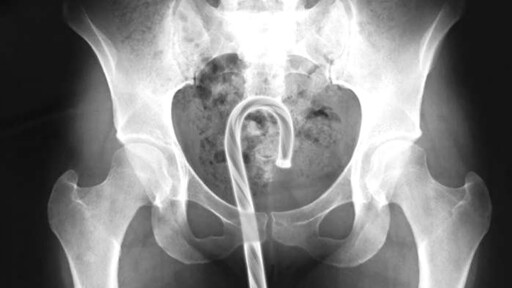

penis: GUITAR STRING

What the…who would…why…and even worse: how to get it out again? No wait, I don’t wanna know.